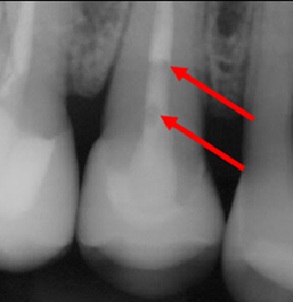

1. Бульбашки на рентгені

На контрольних знімках ендодонтично пролікованого зуба можна побачити дві виражені бульбашки.

Для лікаря це прикра ситуація, яку важко пояснити пацієнту — і, чесно кажучи, саме такі випадки доводять ендодонтистів до розпачу.